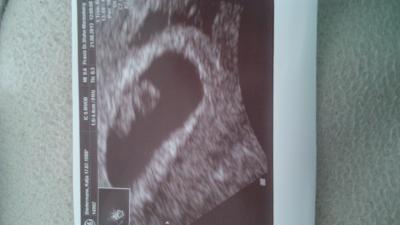

HALLO ihr lieben! Bin gerade zurück vom Frauenarzt. Alles Bestens! Krümel ist schön gewachsen. Bin glücklich Schönen Tag euch.

Bild zu Zurück vom FA! - Forum für April - Mamis

Juhu, das ist so ein schönes Foto von Deinem Krümel. Freu mich mit Dir.